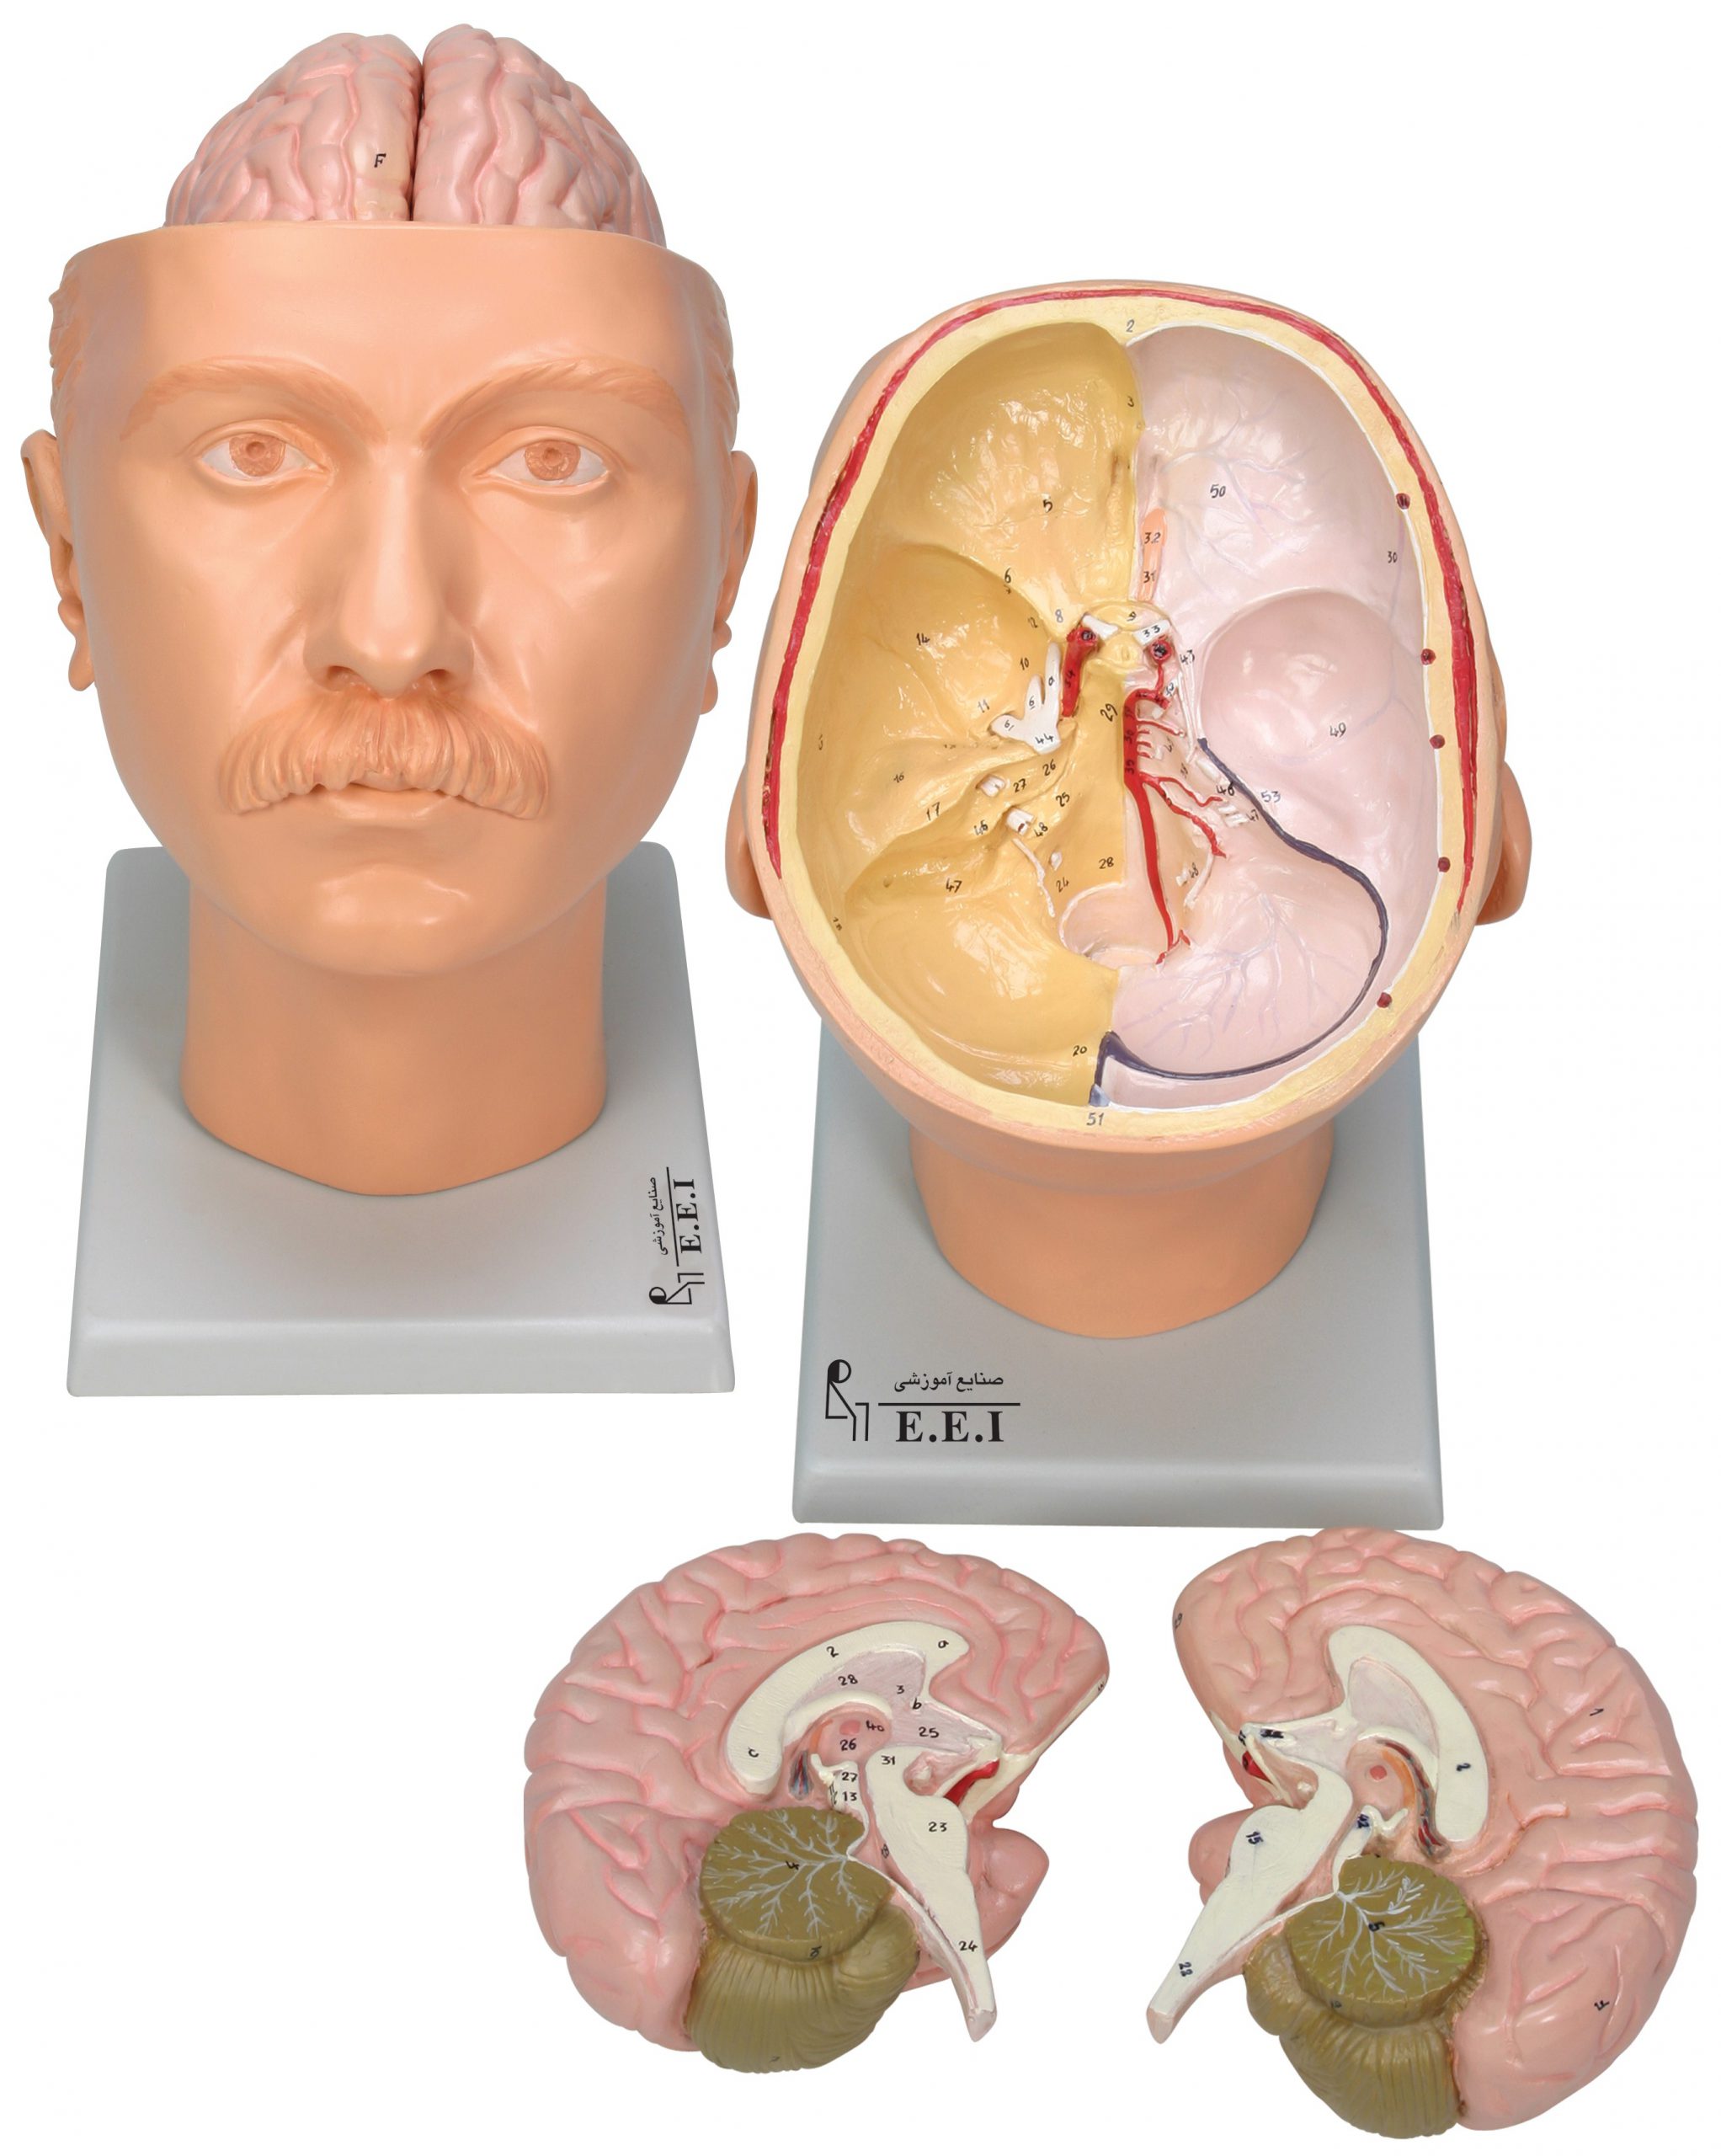

مولاژ کلمه ای فرانسوی به معنای قالب است. آناتومی بدن انسان با تجهیزاتی مانند مولاژهای پزشکی یا کالبدشناسی که نمونه هایی تخصصی و شبیه به اندام های بدن انسان هستند، به دانش آموزان و دانشجویان آموزش داده می شود. استفاده از مولاژ در روند یادگیری و آموزش تاثیر به سزایی داشته و تمامی اندام ها را با تمامی جزئیات و با کیفیت بالا می توان مشاهده و بررسی کرد. مولاژها عموما از جنس PVC نشکن، لاستیک یا فوم ساخته شده و دارای رنگ طبیعی و قابل شست و شو هستند. برخی از انواع مولاژها مناسب برای آموزش مراقبت های پزشکی و پرستاری است و امکان تمرین بانداژ، تزریق، CPR، جراحی و... وجود دارد. مولاژها معمولا هر کدام عضوی از بدن را نمایش می دهند و قابلیت تفکیک و مشاهده همه بخش های آن وجود دارد.

مولاژها معمولا با توجه به نوع اعضا و یا دستگاه های بدن در اندازه طبیعی، کوچکتر و یا چندین برابر بزرگتر ساخته می شوند تا امکان مشاهده دقیق اجزای آن ها فراهم شود. برخی مولاژها از چندین قطعه ساخته شده اند که قابلیت تفکیک دارند. علاوه بر نمایش ساختار و نحوه عملکرد اعضای بدن، ماهیچه ها و عضلات بدن را نیز می توان به کمک مولاژها مشاهده کرد.

مولاژها ابزاری تخصصی برای آموزش دانشجویان پزشکی، دندان پزشکی، پرستاری و مامایی است. همچنین در مدارس و سایر مراکز آموزشی میتوان از انواع مولاژها برای بهبود یادگیری و آموزش بهره برد. در کلینیک های زنان و زایمان، دندان پزشکی، سالن های تشریح، بیمارستان ها و آزمایشگاه ها نیز مولاژهای مراحل حاملگی، انواع دندان و بیماری های آن کاربرد دارند.